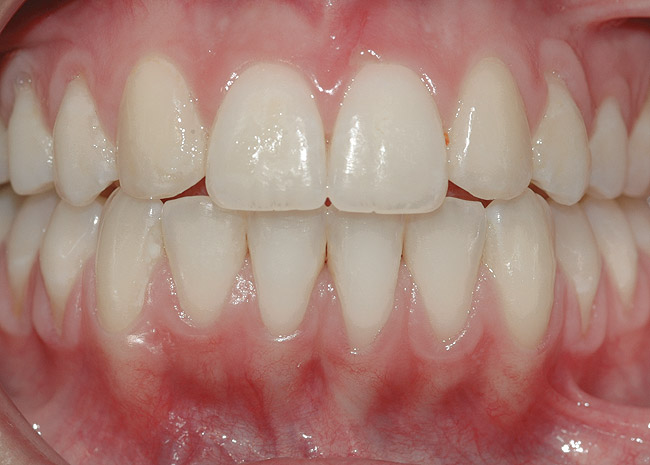

CASE 2 Fig 4. Post-orthodontic Miller Class II recession for which orthodontic treatment was not recommended. Clinical view 3 years after orthodontic treatment, showing relapse in teeth alignment and GR on lower left central incisor.

Figure 4